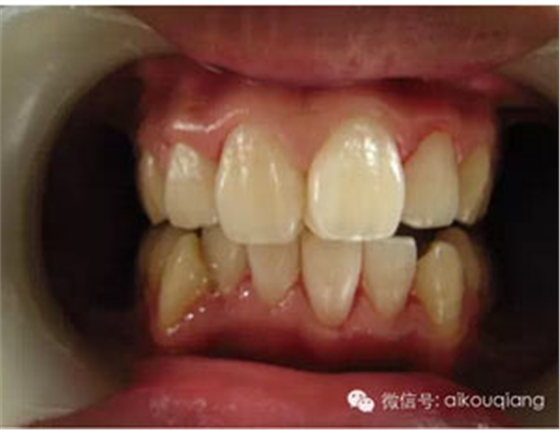

定期洗牙是目前最有效的治療牙周疾病的方式。下面是洗牙前后的對(duì)比圖:

洗牙(潔治)后,潔白如一

洗牙(潔治)后效果很明顯